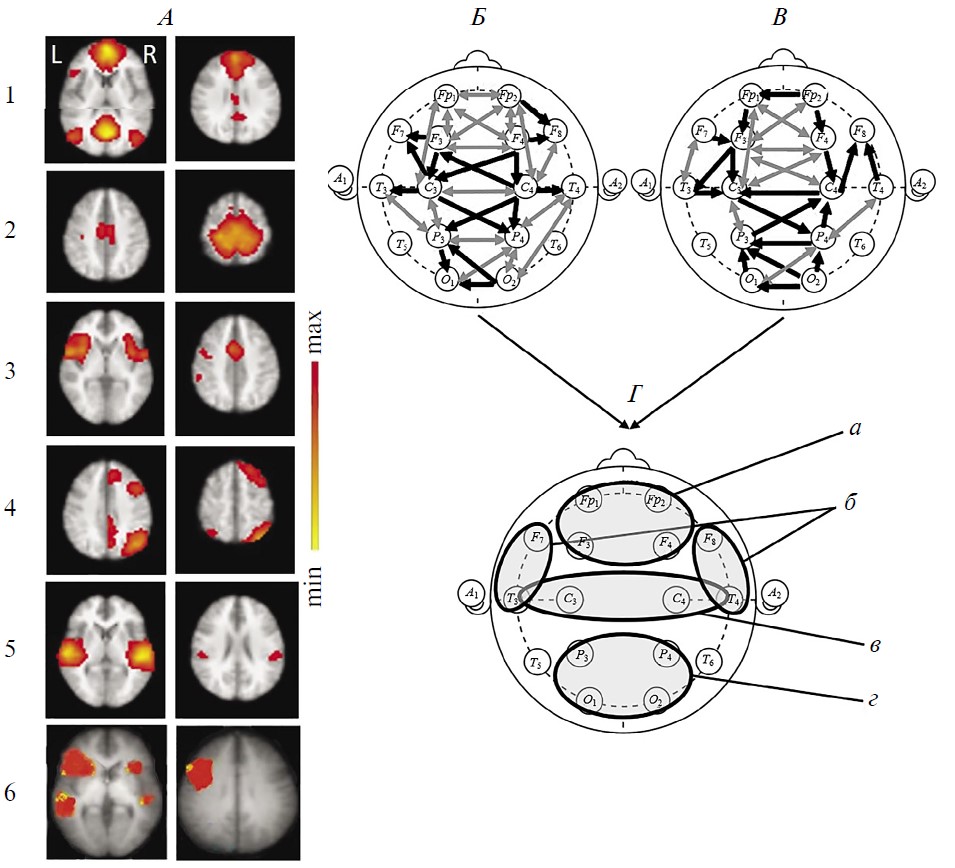

Наблюдение 2. Мужчина 31 года перенес закрытую ТЧМТ с ушибом левой лобной доли, ДАП, множественными мелкими корково-подкорковыми геморрагическими очагами, развившейся впоследствии гидроцефалией.

Через 4.5 года после травмы, при исследовании до рТМС, уровень сознания пациента оценивался как MCS– по шкале CRS-R или акинетический мутизм согласно [37] (табл. 1). В двигательной сфере у него выявлялся преимущественно правосторонний тетрапарез с повышением мышечного тонуса. На МР-томограммах (рис. 4) выражено расширение боковых желудочков; атрофические изменения вещества мозга, превалирующие в лобных долях.

Рис. 4. Динамика сетей покоя функциональной магнитно-резонансной томографии (фМРТ) и коннективности ЭЭГ-диапазона 1–15 Гц в наблюдении 2.

A — исследование 1 (до терапевтической ритмической транскраниальной магнитной стимуляции (рТМС)), состояние акинетического мутизма; Б — исследование 2 (через 17 дней после курсовой рTMС), состояние мутизма с эмоциональными реакциями. I — RSN фМРТ: 1 – DMN, 2 – сенсомоторная, 3 – сеть управляющих функций (исполнительного контроля), 4 – лобно-теменная, 5 – речевая, 6 – слуховая. Шкала справа как на рис. 1. II — коннективность ЭЭГ покоя в непрерывной записи. III — коннективность ЭЭГ покоя в режиме псевдо-ВП. Обозначения линий см. рис. 1 и 2.

Спустя 17 дней после курсовой рТМС (10 сеансов в зонах F3–F4) в клинической картине пациента отмечено улучшение в пределах MCS– (по шкале CRS-R) в виде появления эмоциональных реакций (табл. 1). Снизился исходно повышенный мышечный тонус.

Сети фМРТ покоя (рис. 4, I) и до, и после рТМС были представлены только отдельными асимметричными компонентами. До терапии 5 из 6 исследуемых RSN: DMN, сенсомоторной, управляющих функций, лобно-теменной и речевой. За исключением DMN и лобно-теменной, они выражены в левой гемисфере. Наиболее отчетливой была динамика слуховой сети (появление приближенных по конфигурации к норме ее двусторонних компонентов) (рис. 4, Б, I), сопряженной по данным литературы, с активностью лимбической системы [56–58]. Интенсивность большинства RSN имеет тенденцию к снижению после рТМС (рис. 3), за исключением ее нарастания для левой лобно-теменной сети.

Структура коннективности ЭЭГ и при непрерывной записи, и в режиме псевдо-ВП отлична от нормы в обоих исследованиях (рис. 4, II и III). Однако ее изменения более динамичны по сравнению с сетями фМРТ. До рТМС отмечается редукция межполушарных связей, в первую очередь в лобной зоне межсетевого взаимодействия, при сохранности затылочно-теменного локуса. В режиме псевдо-ВП не выражены связи правого височно-передневисочного локуса. Наряду с этим представлены и даже патологически повышены по количеству связи в левом полушарии.

После рТМС коннективность ЭЭГ поменяла свою топологию и латерализацию. Важно отметить появление хотя и ослабленного локуса межполушарных связей в лобных областях при уменьшении активности затылочно-теменного. Инвертировались также внутриполушарные связи: явно увеличились в правом полушарии при их выраженной редукции в левом. Эти изменения отражают формирование также отличного от нормы, но иного по своему содержанию функционального состояния.

Таким образом, менее выразительная (по сравнению с наблюдением 1) позитивная динамика сознания в пределах MCS– в наблюдении 2 сопряжена с активизацией лишь отдельных дополнительных компонентов RSN фМРТ, за исключением появления симметричных составляющих слуховой сети, в сочетании с восстановлением единичных, присущих норме, межполушарных связей ЭЭГ.

Рис. 1. Функциональные сети функциональной магнитно-резонансной томографии (фМРТ) и коннективность ЭЭГ-диапазона 1–15 Гц у здоровых испытуемых в состоянии покоя (n = 15).

А — усредненные по группе испытуемых RSN фМРТ: 1 – DMN, 2 - сенсомоторная, 3 – сеть управляющих функций (исполнительного контроля), 4 – лобно-теменная, 5 – слуховая, 6 – речевая. Шкала справа характеризует уровень максимальной интенсивности сети. Б, В — усредненная в этой же группе испытуемых коннективность ЭЭГ по корреляции Пирсона. Черные линии — однонаправленные связи, серые — двунаправленные, согласно методу причинности Грейнджера. Б — коннективности, рассчитанные на непрерывных записях, В — в режиме псевдо-ВП. Г — зоны концентрации функциональных связей ЭЭГ: а — лобные, б — височно-передневисочные, в — центральные, г — затылочно-теменные.

Рис. 3. Показатели максимальной интенсивности сетей покоя функциональной магнитно-резонансной томографии (фМРТ) здоровых испытуемых и пациентов с ТЧМТ.

I — динамика интенсивности в наблюдении 1, II — в наблюдении 2. Серые точки — значения этого показателя в группе здоровых испытуемых. Сети покоя фМРТ: 1 – DMN, 2 – сенсомоторная, 3 – сеть управляющих функций (исполнительного контроля), 4 – лобно-теменная, 5 – слуховая, 6 – речевая.